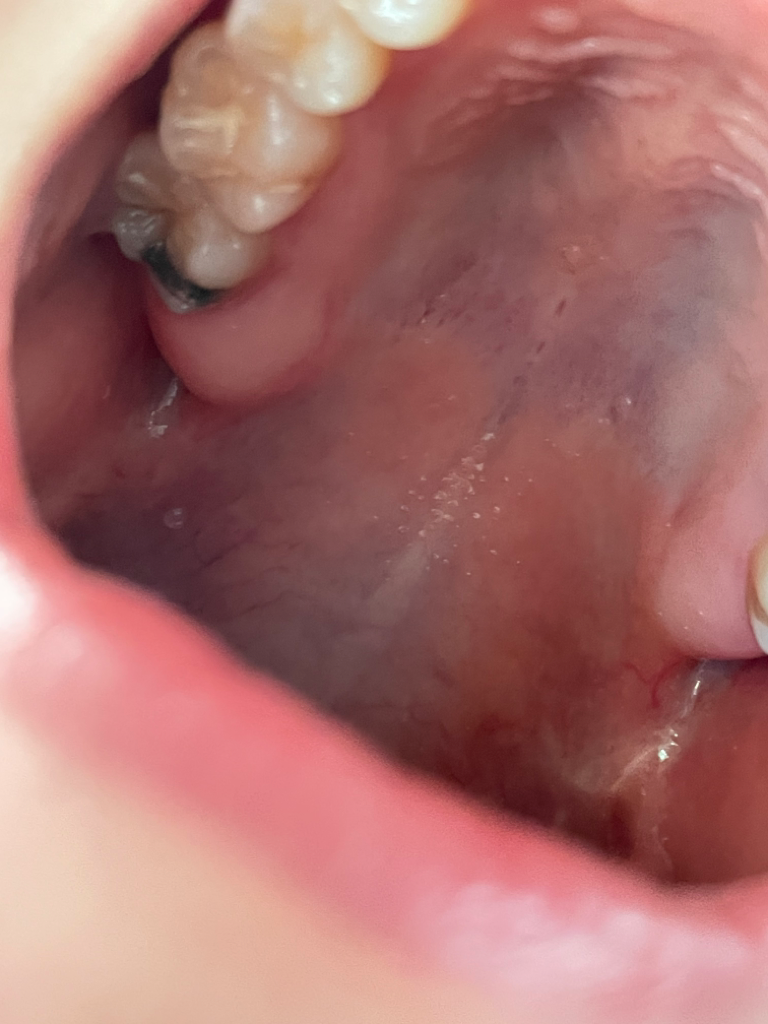

치아가 보니까 부분이 검은색인데 , 이가 썩은건가요?

끝에 이가 썩은건가요?? 아프지는 않아요!!

며칠전에 다른 치아 신경치료로 치과갔을때는 선생님께서 아무말씀 없으셨는데 , 다시 치과 내원해야할까요?

사진이 흐려서 정확하지는 않지만 충치가 아니라 예전에 아말감치료를 받으셨던 것으로 보입니다

끝에 검게 보이는 것은 아말감으로 떼운것 같습니다.

아마 충치가 아니라면 아말감이라는 재료인거 같습니다. 사진상으로 크게 문제가 잇어 보이진 않습니다.